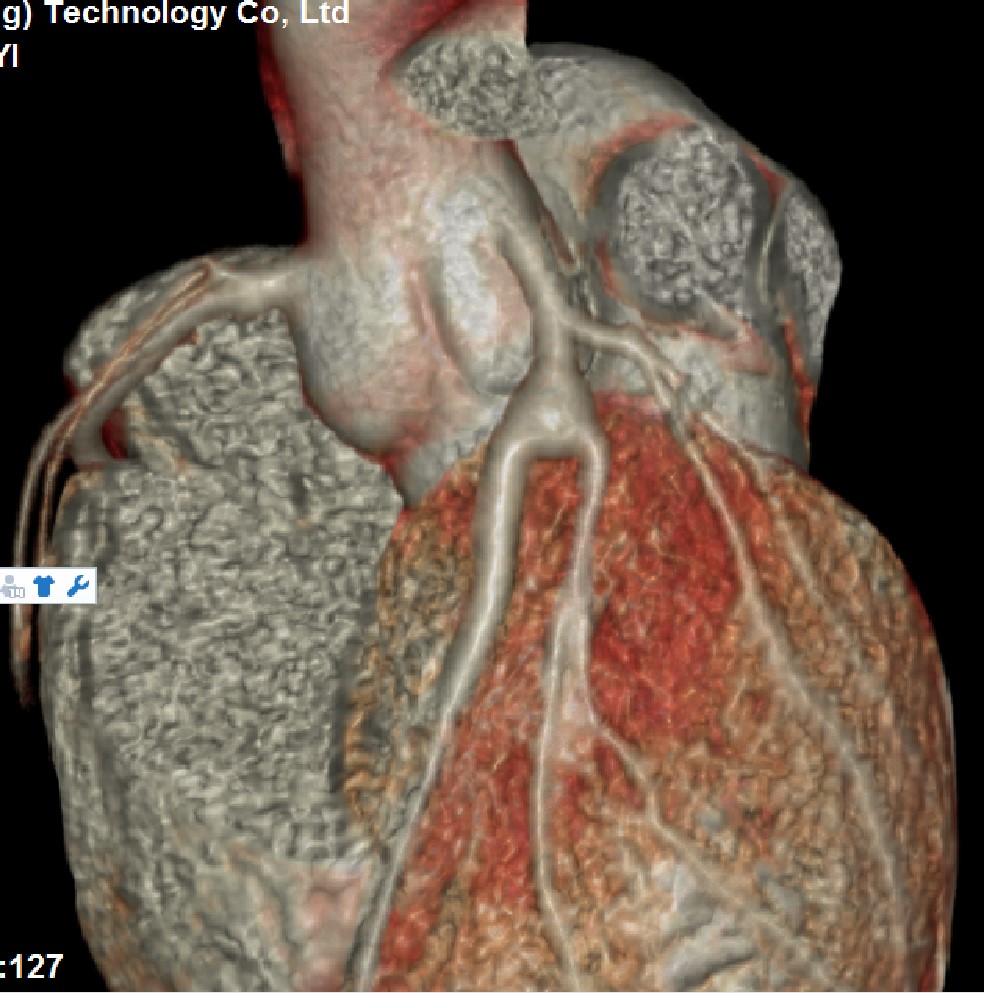

史。化验回报:C反应蛋白 2.27 mg/L (0-3mg/L),血沉(ESR) 20 mm/h(0-15 mm/h), NT-proBNP670 pg/ml,抗核抗体、ANA及相关免疫指标为阴性。术后5天完善冠脉CTA提示前降支近段冠状动脉瘤(图5)。

图5 冠状动脉CTA可见前降支近段瘤样扩张